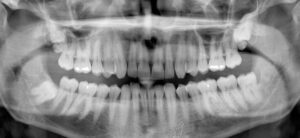

A panoramic dental X-ray provides a broad view of the entire mouth in a single […]

Panoramic dental X-rays are a valuable diagnostic tool in oral healthcare, offering a complete view […]

Panoramic dental X-rays are a type of imaging that captures a complete view of the […]

A panoramic dental X-ray is an important step in maintaining good oral health and preparing […]

Dental health plays an essential role in overall well-being, and one of the most useful […]

Dental health is a crucial aspect of overall well-being, and modern technology has made it […]

Panoramic dental X-rays have become an essential diagnostic tool in modern dentistry. These advanced images […]

When visiting the dentist, one procedure that often raises eyebrows—not just for its technology, but […]